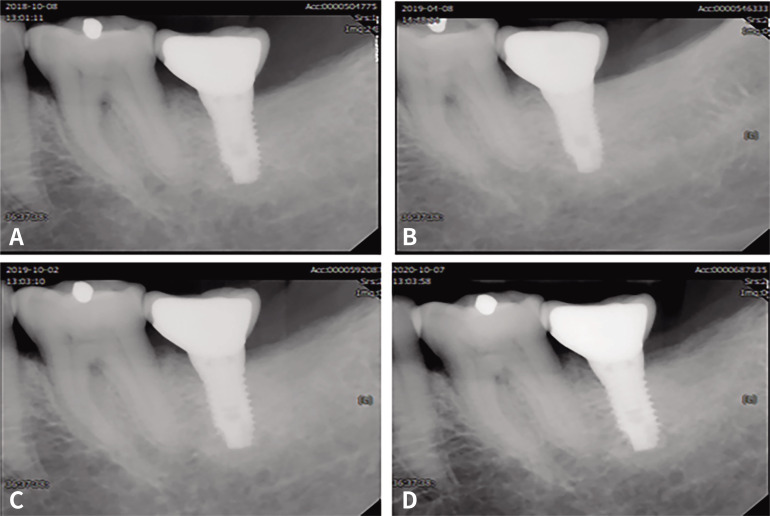

Materials and methods: This study included 71 patients, including 34 with implant-supported metal-ceramic prostheses (control group) and 37 with implant-supported Zr-LiSi bilayered ceramic prostheses (test group). The implant survival rate and incidence of prosthetic and biological complications (veneer fractures, dislodgement of screw-access hole filling material, screw loosening, peri-implant mucositis and peri-implantitis, and marginal bone loss) were investigated. The survival rate was analyzed using Kaplan-Meier survival curves, and the identity between two groups was confirmed by the log-rank test.

Results: Both groups showed a 100% survival rate, whereas the prosthetic survival rates were 77% and 73% for the metal-ceramic and Zr-LiSi groups, respectively. Biological complications did not appear in the metal-ceramic group, and 16.2% of peri-implant mucositis occurred in the Zr-LiSi group, which was significant (P < .05). Prosthetic complications occurred in 5.8% of the metal-ceramic group with veneer fractures and did not occur in the Zr-LiSi bilayered ceramic group.

Conclusion: This study revealed that posterior Zr-LiSi bilayered ceramic implant prostheses showed high survival rates and similar survival rates to metal-ceramic implant prostheses; however, additional consideration should be given to avoid overcontouring. Zr-LiSi bilayered ceramic implant prostheses may be an option for posterior implant-supported prosthetic treatment.